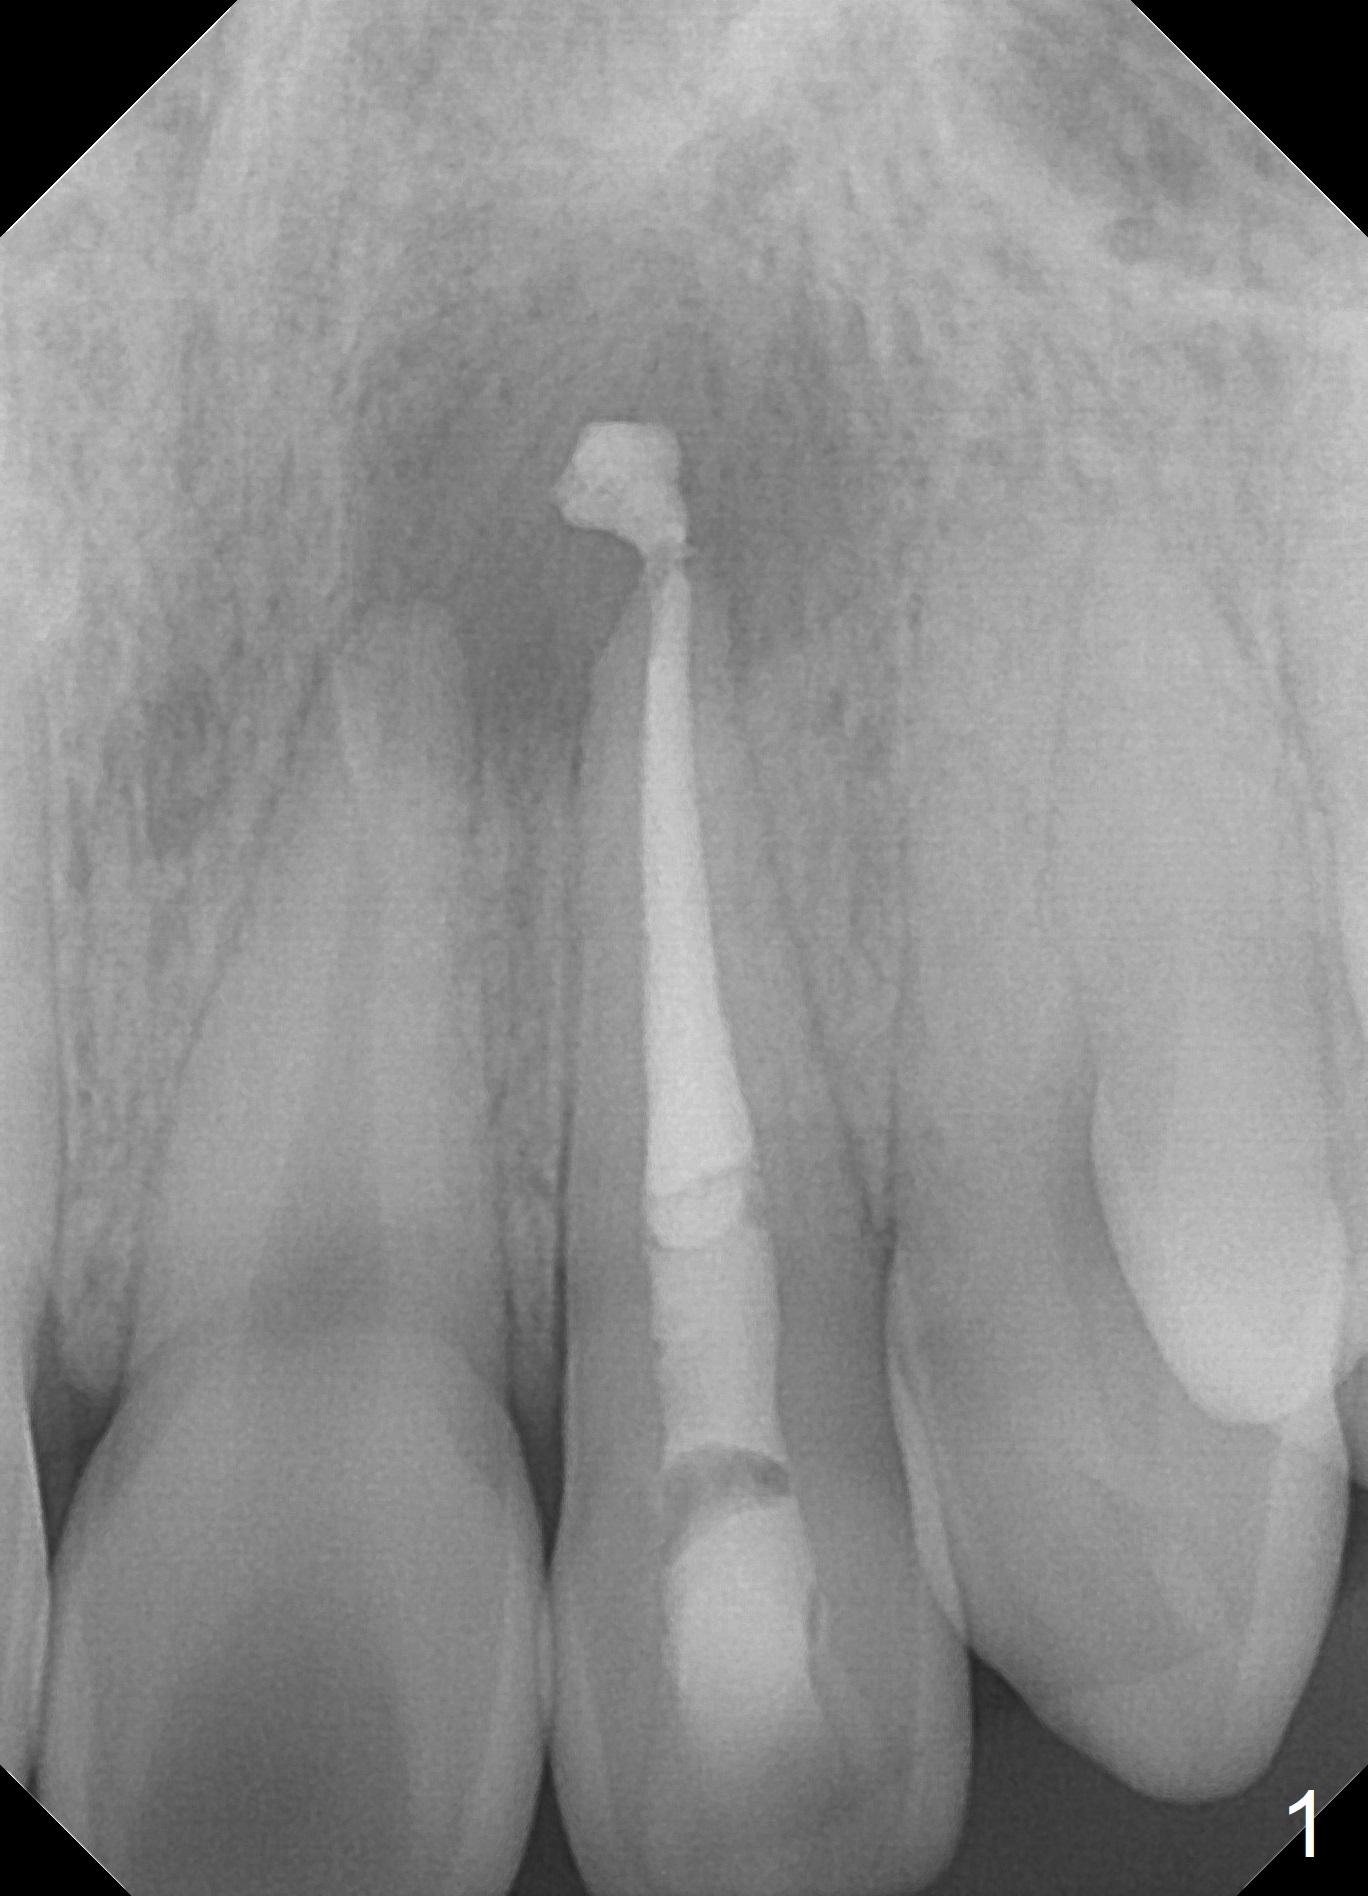

A 18-year-old man develops acute apical periodontitis at #10 several years after phase I and II orthodontic treatment. Fig.1 is taken immediately post RCT with #70 master gutta percha (GP) and 2 medium and 1 fine fine accessory GP. Periapical radiolucency reduces 1 year 9 months postop (Fig.2). The patient reports occasional tingling 2 years 3 months postop (Fig.3).